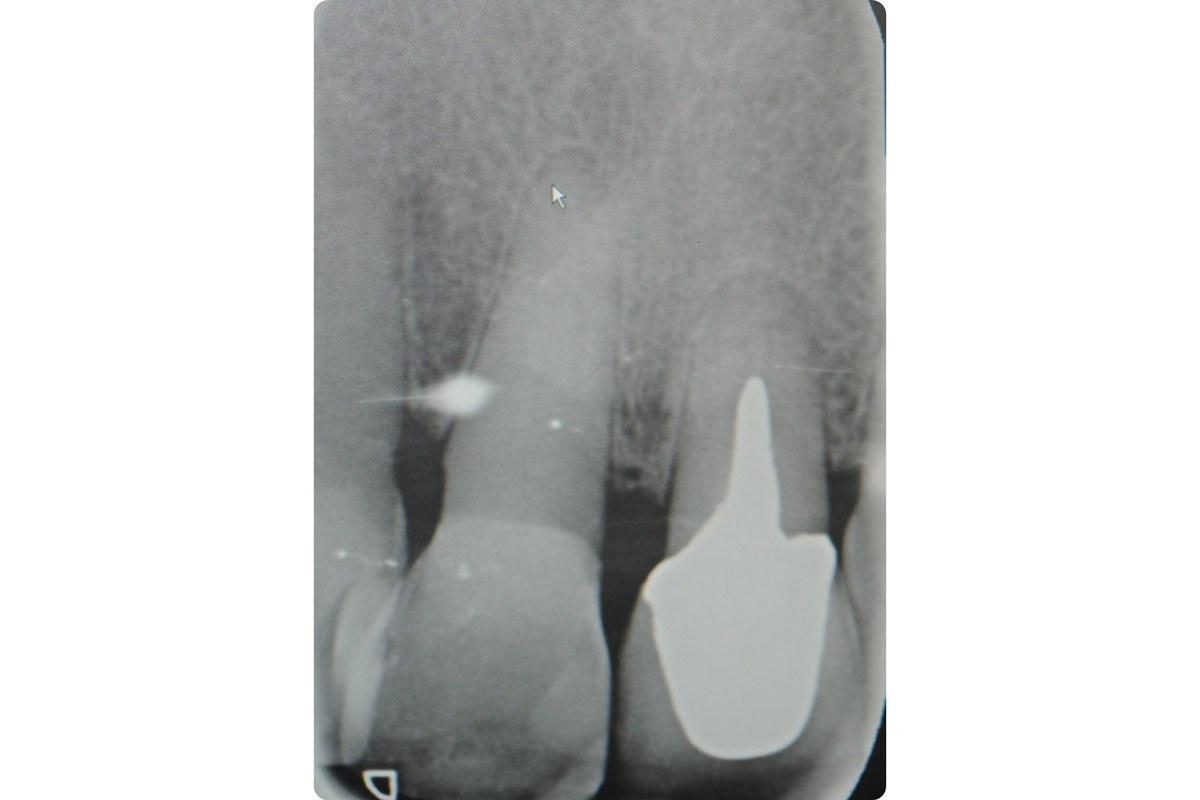

4/18 - X-ray after extractionTooth extraction and socket sealing with mucoderm® - Dr. A. Rossi